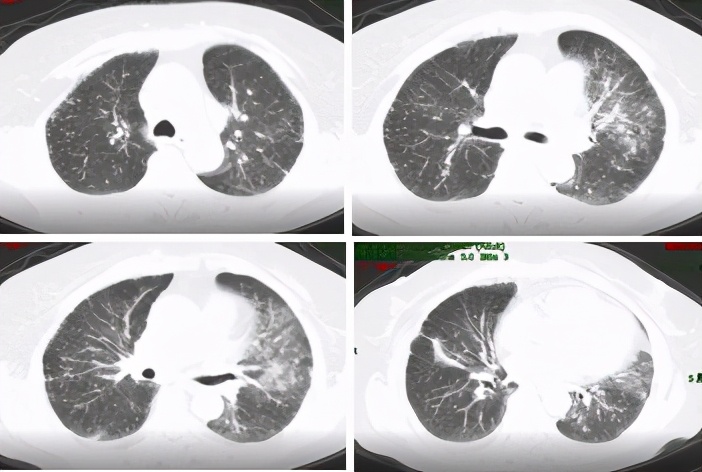

该患者到底是副肿瘤性风湿病综合征,还是肿瘤合并系统性硬化呢?这需要在进一步的治疗中验证。由于该患者及家属不愿行盆腔占位活检,放弃了放化疗等肿瘤相关治疗,因口服激素及复方环磷酰胺后呼吸困难好转,愿意继续行系统性硬化病的相关治疗:泼尼松片(40mg qd,逐渐缓慢减量),复方环磷酰胺片100mg qd (长期口服未减量),乙酰半胱氨酸600mg tid,百令胶囊4颗 tid。经上述治疗后,患者呼吸困难进一步好转,后于治疗后约1个月及3个月后复查胸部CT提示肺部病灶减少,胸水逐渐减少至基本吸收。原则上副肿瘤综合征肿瘤治疗后风湿病表现才明显好转,只是抗风湿治疗好转并不能证明是副肿瘤综合征。通过治疗反应,考虑患者为肿瘤伴发系统性硬化可能性大。

图6:复查胸部CT(2017-05-26)肺部病灶进一步吸收,胸水基本吸收